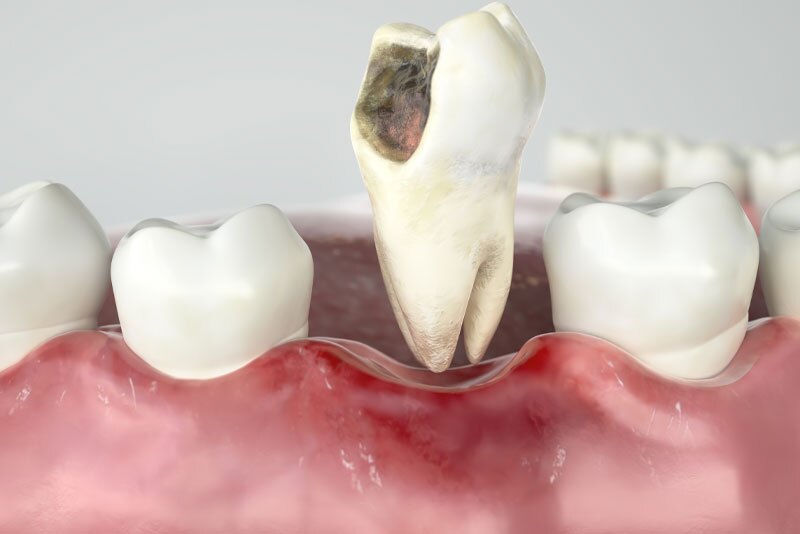

The decision to perform an extraction is typically straightforward when a tooth is impacted by significant decay, severe periodontal disease or a fracture. In addition, impacted wisdom teeth nearly always need to be extracted. Digital X-rays are used to analyze the underlying structures and determine if the tooth can be saved. If there is a pulp infection without a tooth fracture, root canal therapy is a highly successful method for preventing extraction. Extraction of normal teeth may be required for orthodontics, full mouth dental implants or when a primary tooth hasn’t fallen out and is stopping a permanent tooth from erupting. At Kari Mann Dental Studio in Cape Coral, our goal is always to save natural teeth, however, if conservative treatment is ineffective, extraction may be necessary. Extraction of a damaged or abscessed tooth can prevent more serious issues from impacting other teeth, your oral health and even your physical health. Regardless of the reason, Dr. Kari Mann has extensive expertise performing gentle tooth extraction in Cape Coral, FL. With a local anesthetic and sedation if you need it, tooth extraction will alleviate acute or chronic tooth pain and restore your oral health.

Due to the position at the back of the mouth, lack of space or an obstruction, wisdom teeth (third molars) frequently become partially or completely impacted. Impacted wisdom teeth are hard to clean so they’re prone to bacteria buildup. This can lead to decay, pain, swelling, gum disease and cysts that can harm adjacent teeth and bone. Dr. Kari Mann offers wisdom tooth removal in Cape Coral, FL under local anesthesia and sedation, however, more complex cases may be referred to an oral and maxillofacial surgeon.

damaged tooth graphic